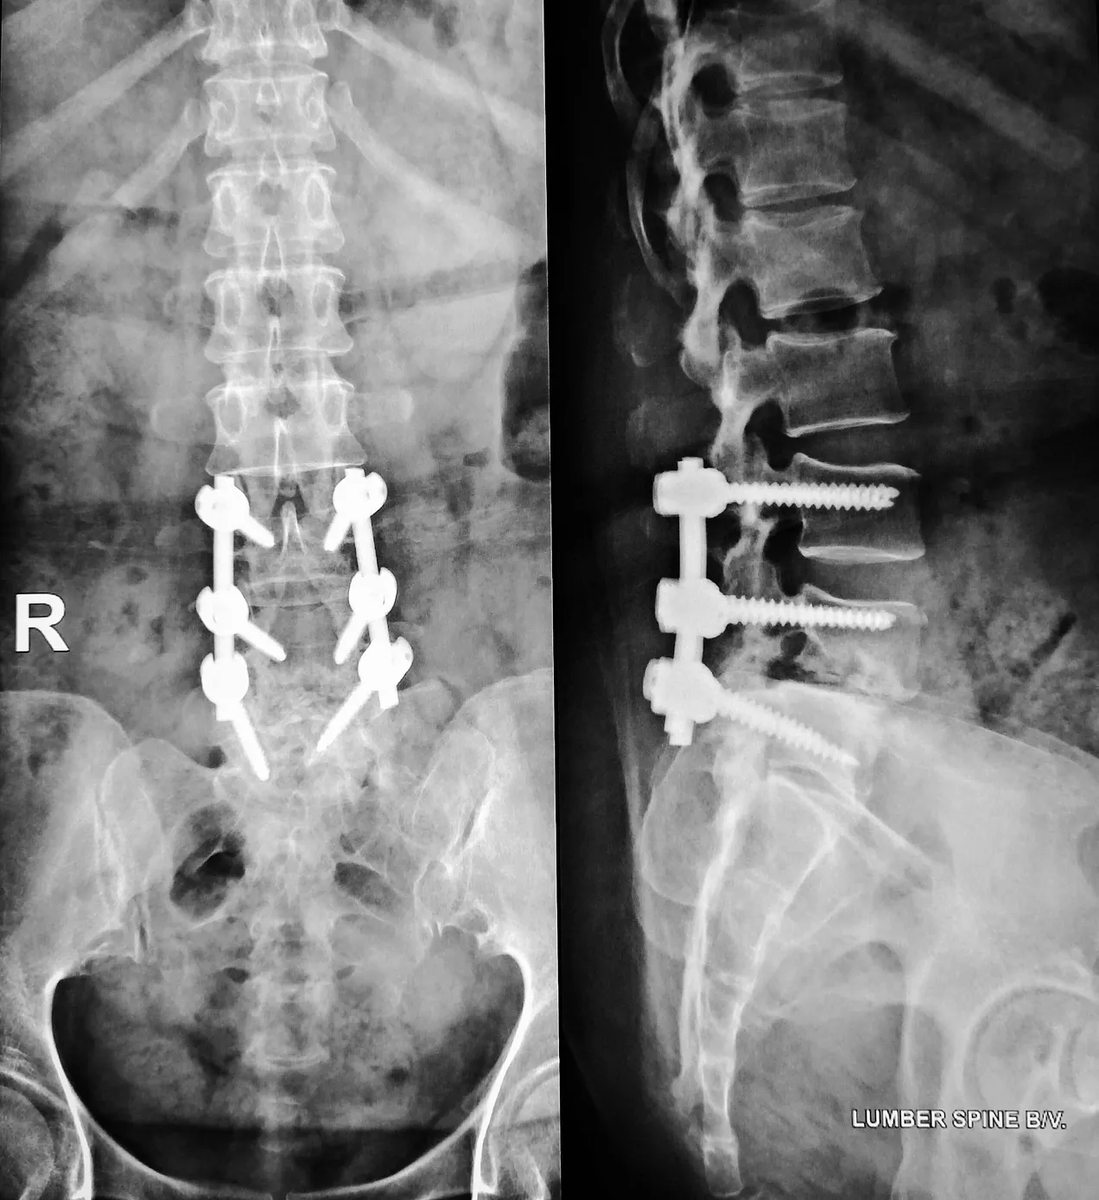

And during Dr. Delashaw’s tenure in Seattle, rates of medically unjustifiable lumbar fusions surged!Image

Spinal surgeries can be put into the following three categories:

• Emergency fracture repairs—completely necessary

• Laminectomies—often effective, especially in the lumbar spine

• Fusions and hardware-heavy procedures—the most dangerous and least justified

The long-term risks of fusions are absolutely brutal:

• Loss of mobility

• Adjacent vertebrae breaking down

• Hardware failure

• Repeat surgeries

• Chronic pain

• Nerve injury

• Arachnoiditis

• Metallosis from toxic implant metals